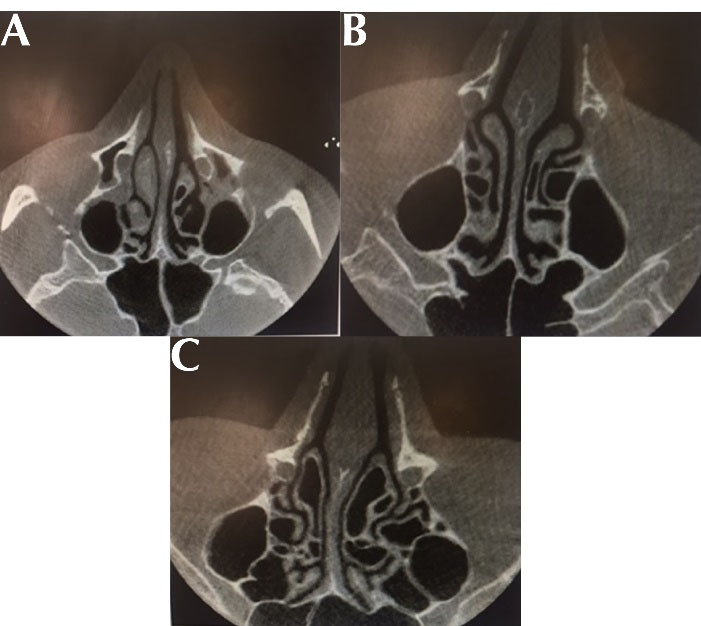

All CT images on the monitor (Philips 202EL2SB, 20 inches) in the axial section were examined for the presence and type of the pneumatization of the middle concha (concha bullosa) by oral and maxillofacial radiologists. Concha bullosa types were divided into three groups of bulbous (The pneumatization of the onion-shaped part of the middle concha, Figure 1A), lamellar (The pneumatization of the lamellar (base) part of the middle concha, Figure 1B), and extensive (The pneumatization of both the lamellar and bulbous parts of the middle conical, Figure 1C) according to (3). Descriptive statistics such as the mean, standard deviation, and the frequency and the percentage table were used to present the data. In addition, the Chi-square test and independent t-test were performed by SPSS (version 22) and a P value less than 0.05 was considered statistically significant.

Figure 1.

(A) Bulbous-Type, (B) Lamellar-Type and (C) Extensive-Type Concha Bullosa in CBCT Axial Section. Note. CBCT: Cone-beam computed tomography.